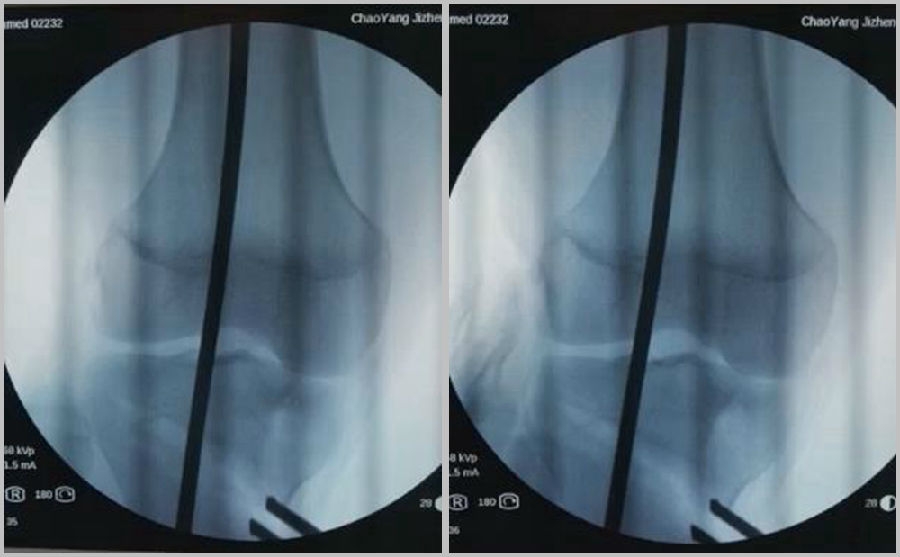

(2)Ⅱ型骨折

当出现Ⅱ型骨折时要特别注意,因为此时截骨的远端就是骨折的远端,近端只有上胫腓周围骨筋膜存在,所以相对来说Ⅱ型骨折并不稳定。

首先用拉力螺钉复位,调整好力线。然后做结构性植骨,延迟负重,所谓延迟负重就是延迟到外侧合页和上行截骨线处达到初始愈合,然后再让患者进行负重。如果不做结构植骨加延迟负重,就会出现一些非常严重的现象,如不愈合。

拉力钉复位,结构性植骨

左侧患者未植骨正常负重,术后4个月不愈合;右侧患者非结构性植骨过早负重,术后1年未愈合